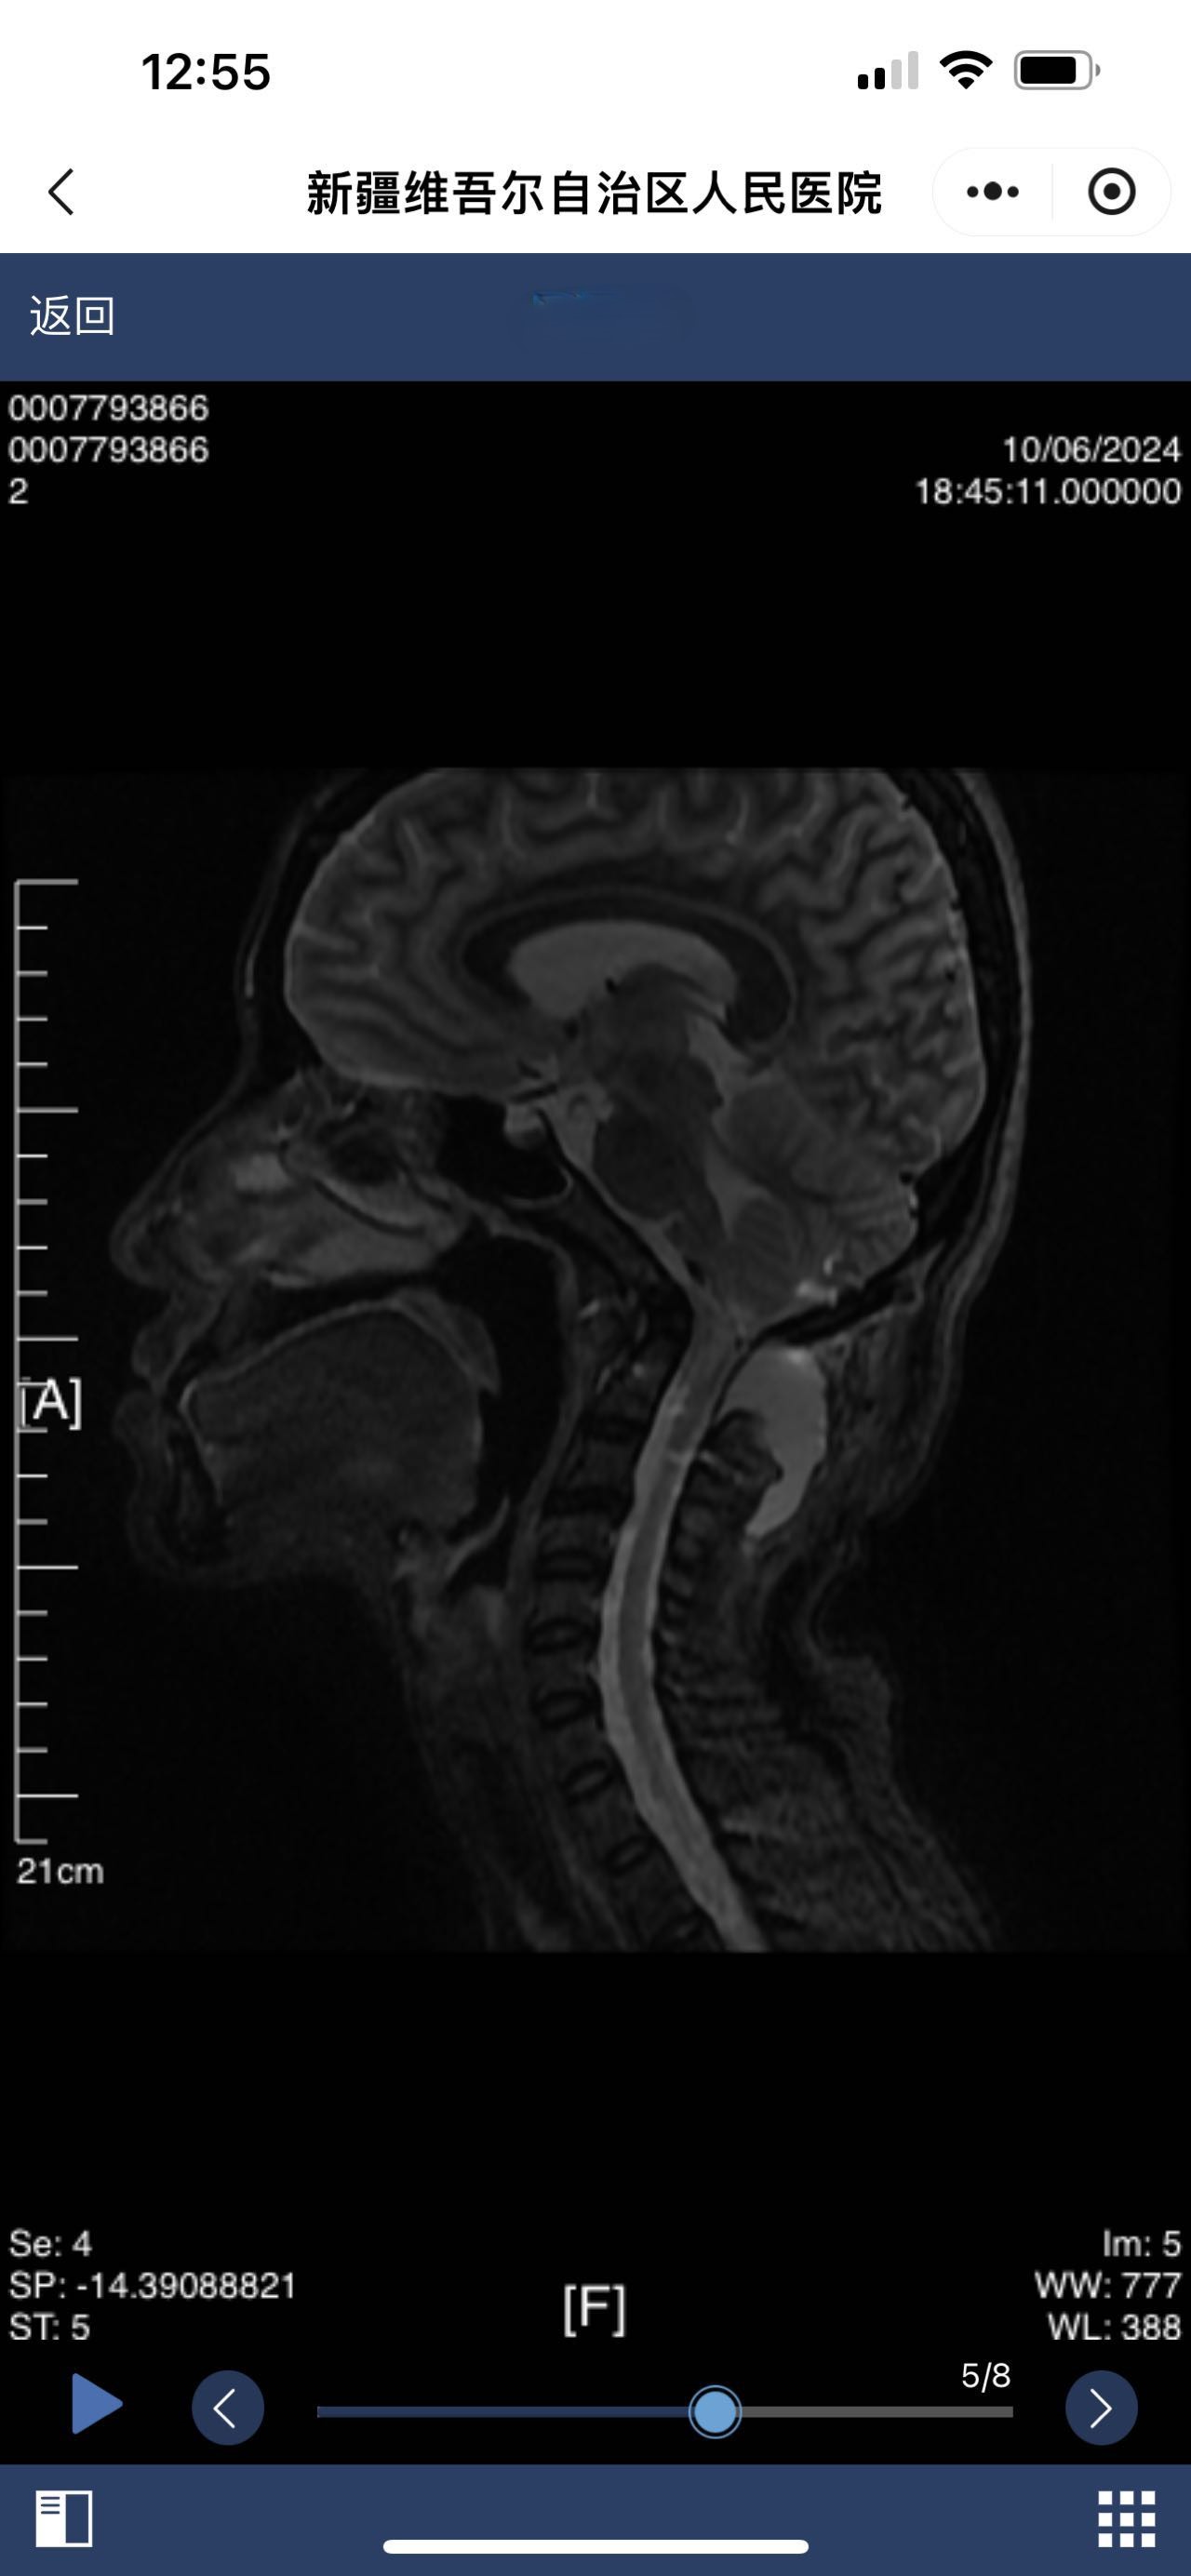

• 术后影像:

• 2024.10.06,积液范围略小。